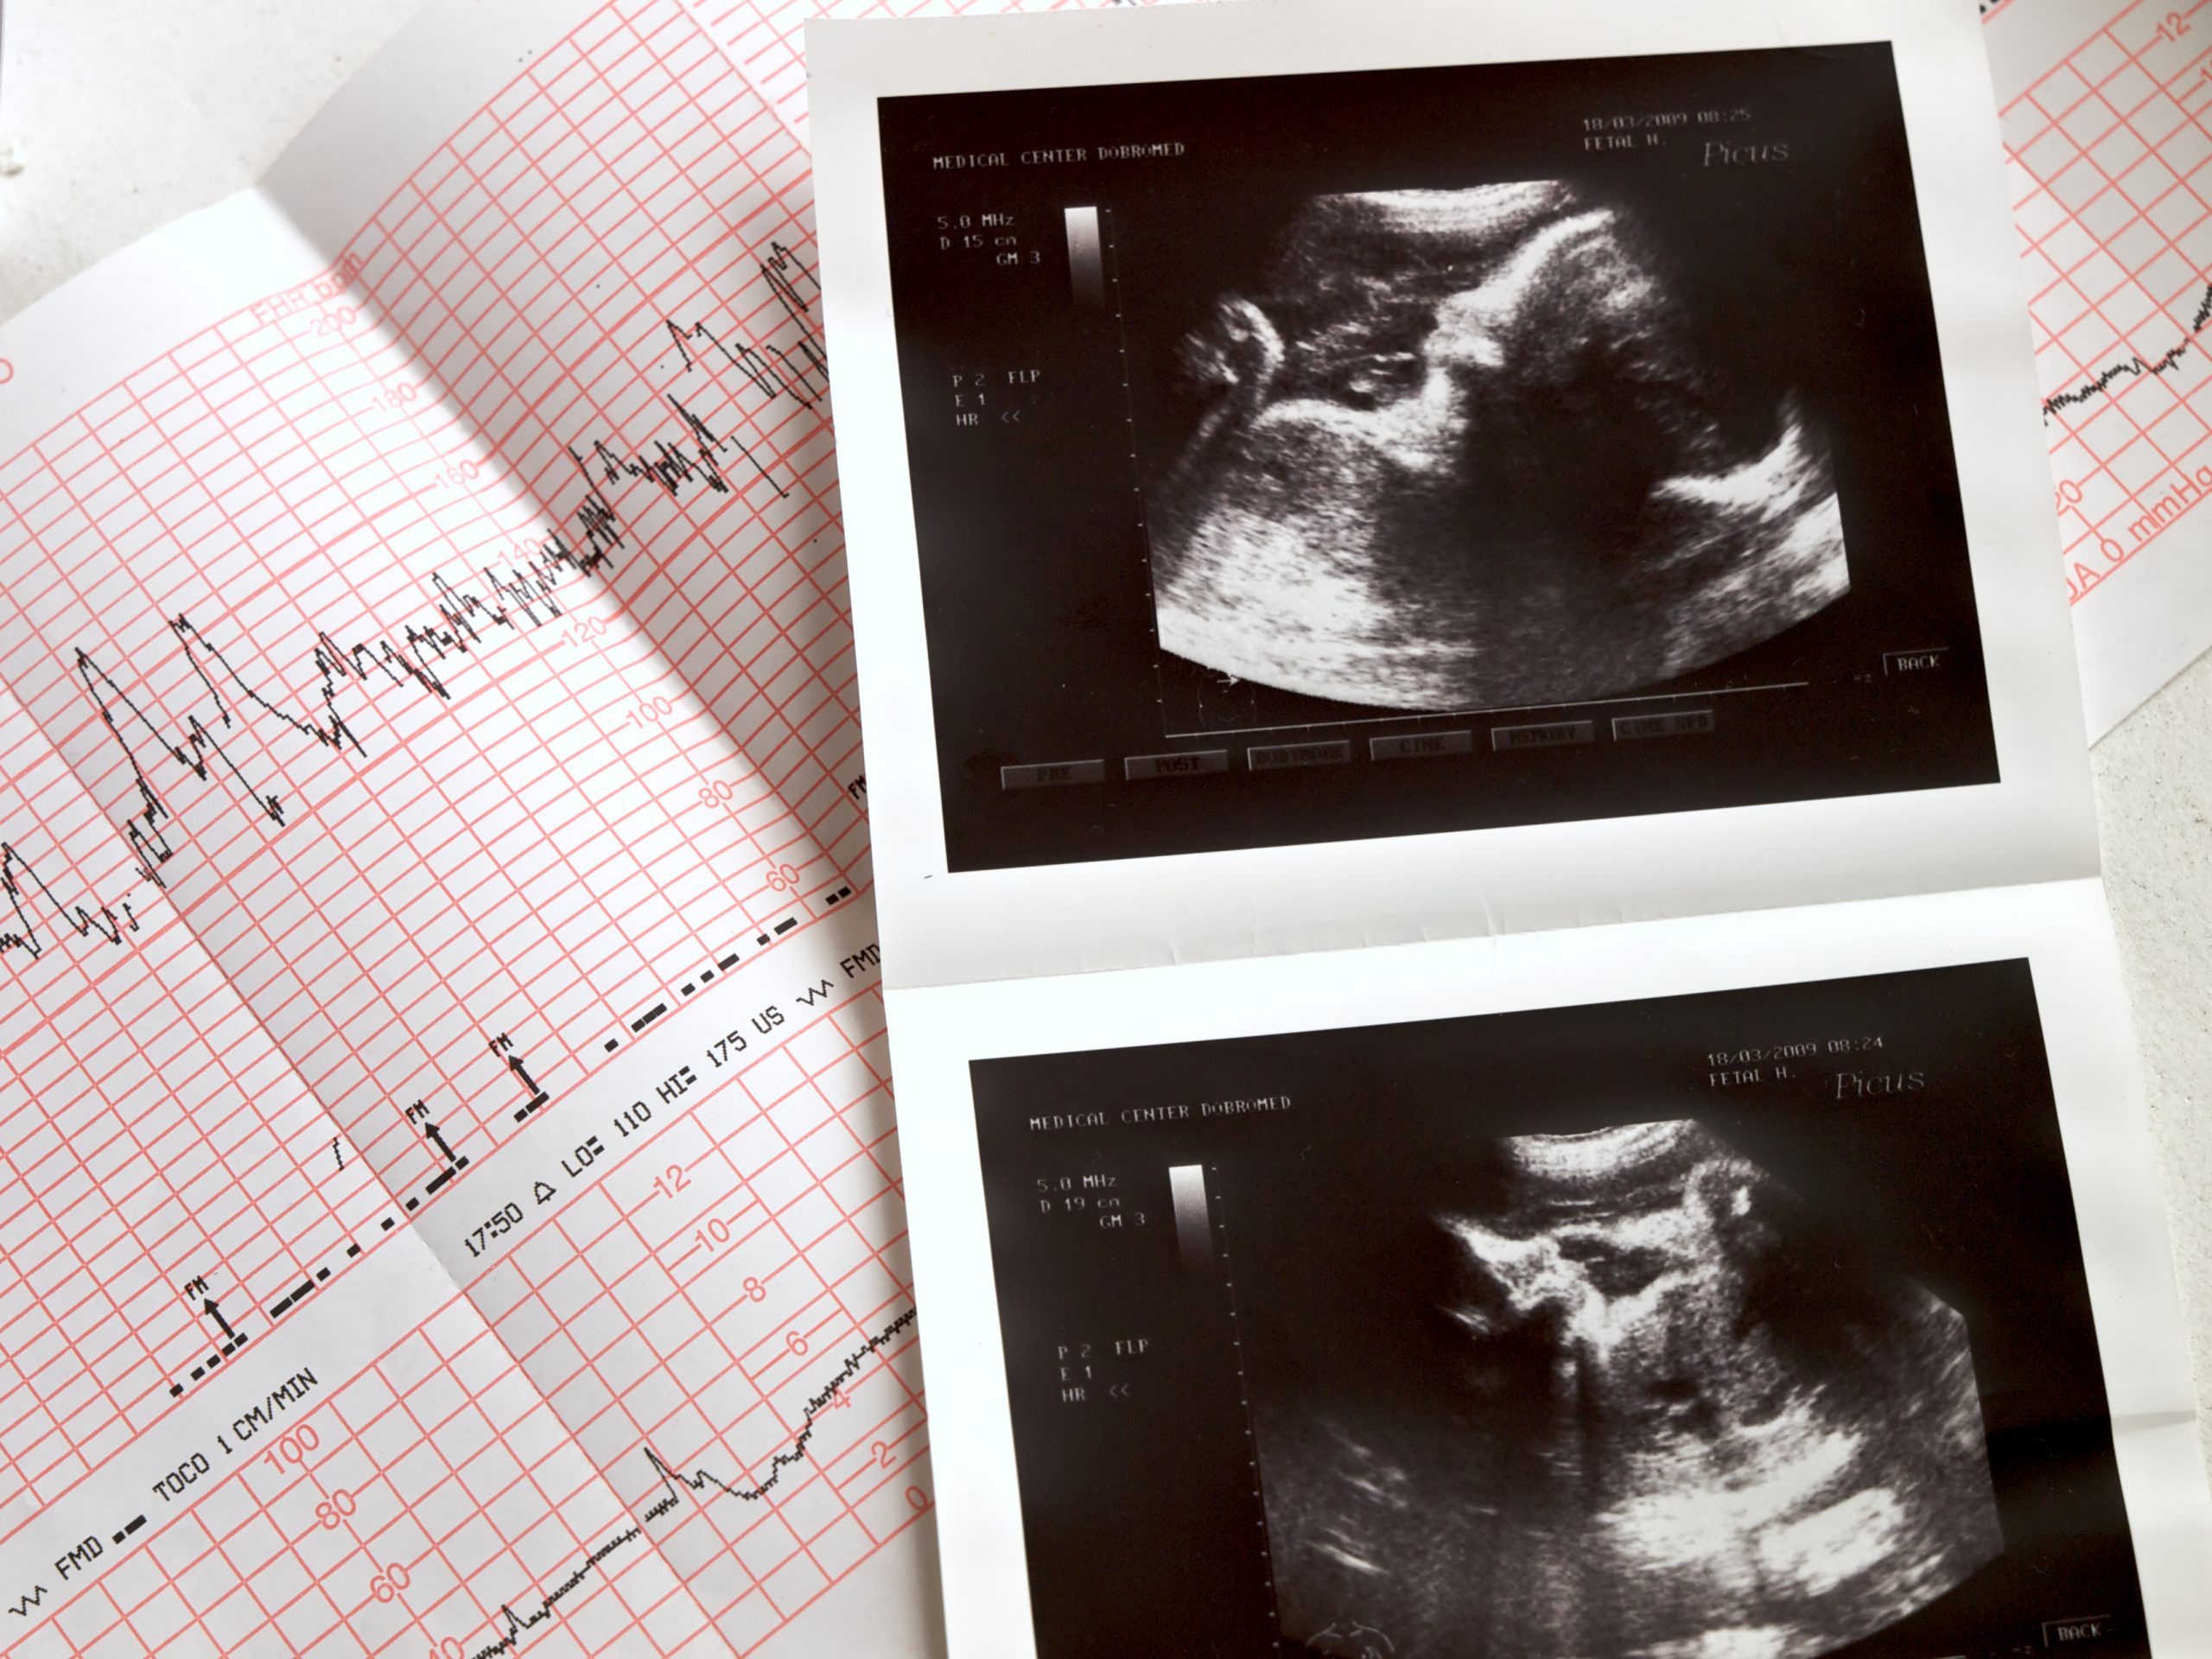

Exames realizados

no Santa Joana

Aqui estão alguns dos exames que oferecemos que são importantes para o seu pré-natal:

• Ultrassom Transvaginal: Avaliação precoce do

embrião, útero, ovário e posicionamento.

• Ultrassom Obstétrico com Doppler: Verificação

de

circulação, crescimento fetal e saúde da placenta.

• Ultrassom Morfológico: Análise detalhada da

anatomia fetal no segundo trimestre.

• Ecocardiograma Fetal: Avaliação do coração do

bebê

para detectar possíveis alterações.

• Outros exames de rotina: Pressão, glicose, anemia, sífilis, entre outros, conforme necessidade médica.